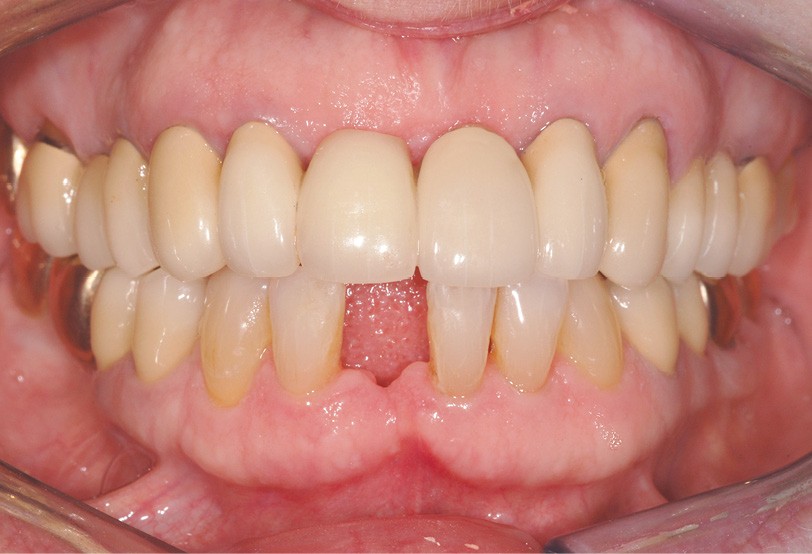

Le cas clinique présenté dans cet article traite de la gestion d’un édentement mandibulaire dans le secteur antérieur, survenu après un accident de la voie publique ayant entraîné une aggravation d’une lésion parodontale existante (fig. 1). Cette pathologie a nécessité l’extraction de la dent qui avait été traitée huit ans auparavant par une attelle-bridge en zircone, compte tenu de l’impossibilité médicale de mettre en place un implant (fig. 2).